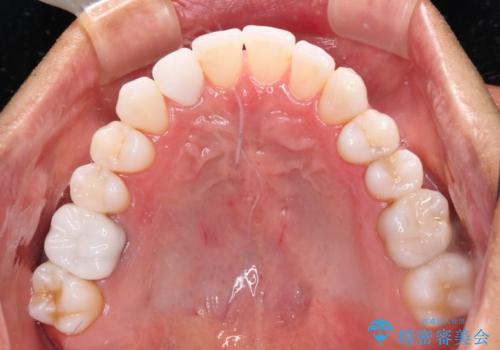

- 治療途中の前歯と上下前歯のデコボコ気にして来院された患者様です。

前歯のデコボコはインビザラインにより歯列を整え、その後に、前歯などをオーダーメイドタイプのオールセラミッククラウンにて補綴治療することとしました。

長時間のマウスピース装着に協力いただき、短期間で歯列をしっかりと改善することができました。

ホームホワイトニングを併用していただいたので、とても明るい口元に仕上がり、患者様には大変満足していただきました。